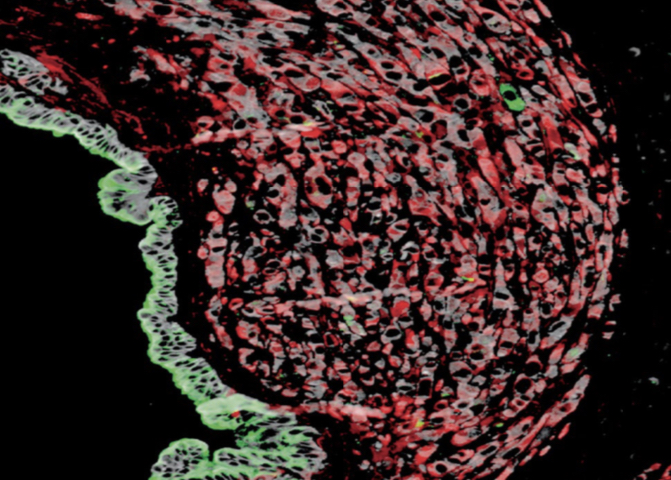

A team of researchers at the ICR and Imperial College London, led by the Scientific Director of the CRUK Convergence Science Centre Prof Axel Behrens, have identified a new potential drug target to treat and stop the spread of pancreatic ductal adenocarcinoma (PDAC), one of the most aggressive and common types of pancreatic cancer.